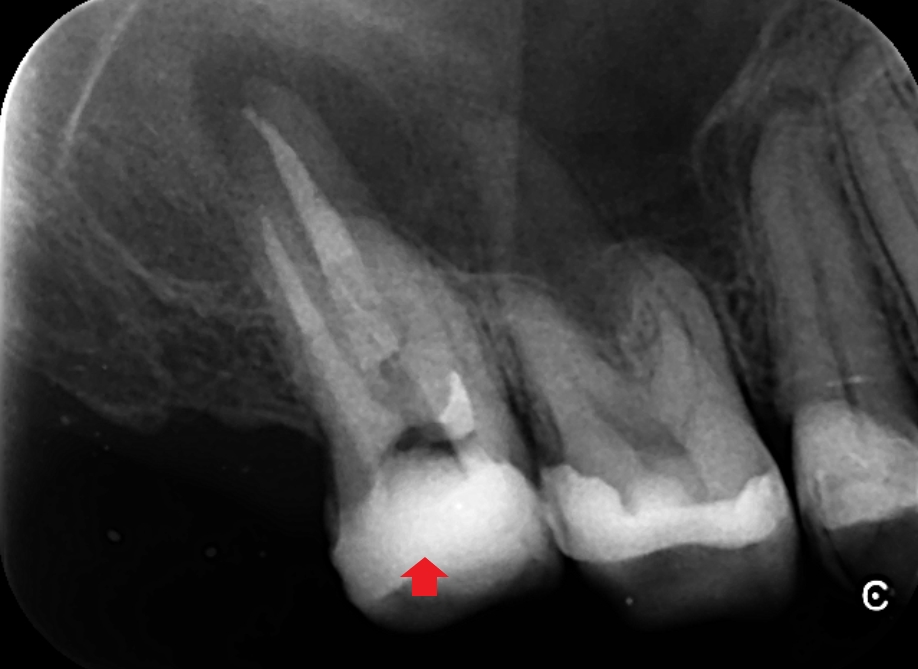

口蓋根は歯科用顕微鏡で歯根破折がみられなかったので、精密根管治療を行いました。画像は根管充填時のレントゲン写真です。